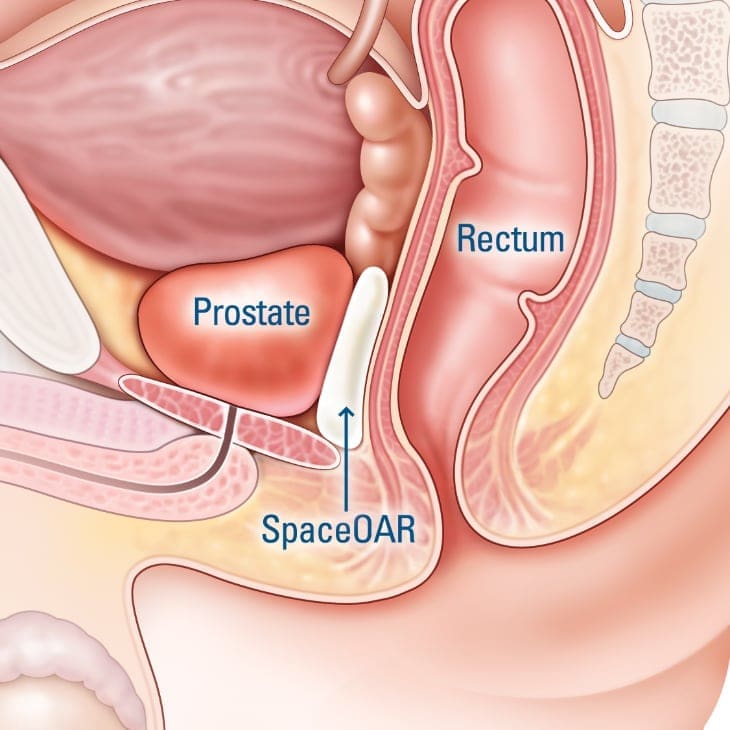

SpaceOAR & Barrigel

Radiation therapy is very effective in treating advanced prostate cancer. At Urology Partners, we help men take extra precautions to protect the rectum and prevent unpleasant post-radiation side effects.

Men can choose to have a soft, absorbable gel—either SpaceOAR or Barrigel—carefully injected into the narrow space between the prostate and rectum before their first radiation treatment. Both gels provide a cushioned barrier that helps shield the rectum from radiation and reduce post-radiation side effects such as rectal pain and bleeding, chronic diarrhea, urinary urgency and leakage, and erectile dysfunction.

Performed under local anesthesia, most men only experience a pin prick or slight pressure during the injection, and generally do not feel any prolonged discomfort during or after the procedure. Patients are able resume their normal activities soon afterward. SpaceOAR and Barrigel are fully absorbed in just a little over six months.